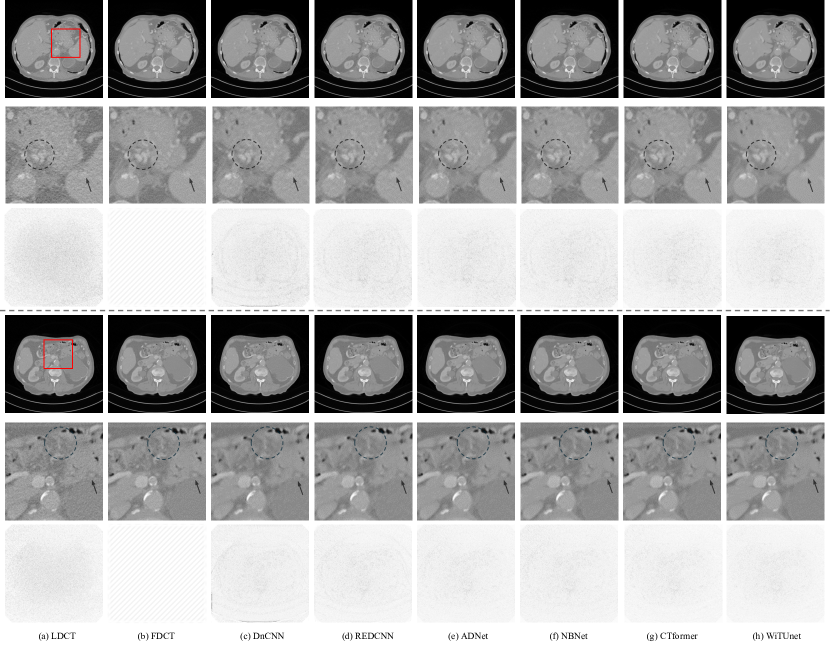

To demonstrate the denoising performance of the method proposed in this study, as well as its ability to suppress noise in LDCT images while retaining rich detail, Figure 5 provides a visualization of denoising results for two slices from the Mayo Clinic 2016 dataset. The regions of interest (ROIs) are demarcated by red dashed rectangles.

The first row, labeled (a) through (h), shows abdominal CT scans from the same anatomical cross-section of a patient, with each column representing a distinct technique or condition. Column (a) shows the original low-dose CT (LDCT) image, which appears noisier with less clarity in the details. Column (b) displays the full-dose CT (FDCT) image, serving as the reference standard with visibly higher clarity and less noise. Columns (c) through (h) present images processed by various denoising algorithms: DnCNN, REDCNN, ADNet, NBNet, CTformer, and WiTUnet respectively. These images exhibit progressive noise reduction and clarity improvement compared to the LDCT image. Beneath the first row, a zoomed-in view of a specific region of interest (ROI) is provided for each technique, allowing for a closer examination of the denoising effects on fine structures within the images. This magnified view facilitates a more detailed comparison of the denoising efficacy, as the subtle textures and contrasts are more discernible. The second row displays the differential images, obtained by subtracting the FDCT images from the denoised results of the respective techniques. These images highlight the differences between the processed images and the FDCT standard, emphasizing areas where noise was reduced or where certain details may have been altered during the denoising process. The variations in grayscale intensity within these differential images correspond to the effectiveness and characteristics of each denoising method. The display window of all images is set to a range of [-160, 240] HU, chosen to best visualize the contrasts and details within the soft tissues and any artifacts present. Additionally, the brightness across all images has been adjusted to maintain a uniform visual standard, ensuring that the comparative differences are not due to variations in image brightness but rather to the denoising algorithms themselves.

Visually, all the compared methods exhibited commendable noise reduction capabilities. However, a detailed examination of the processed images and the magnification of the regions of interest (ROIs) revealed distinct differences between them. For instance, the early denoising network DnCNN, due to its straightforward architecture lacking residual learning, did not achieve denoising performance comparable to more recent models. REDCNN, with its incorporation of an encoder-decoder structure and residual learning, significantly enhanced denoising efficacy. Moreover, ADNet introduced convolutional blocks within its skip connections for better alignment of feature maps between the encoder and decoder, while NBNet, with its attention-guided CNN, bolstered the capture of local details, further improving performance. Despite the CNN-based models excelling in capturing local information, they exhibit certain limitations in perceiving global information. The CTformer, by adopting a Transformer network and its attention mechanism, improved global information modeling capabilities, demonstrating superior denoising performance relative to other models. However, potentially lacking the benefits of a CNN architecture, CTformer might fall slightly short in capturing fine local details. WiTUnet, merging the global information modeling of window Transformers with the local information capture ability of LiPe and utilizing nested dense blocks for effective feature map alignment, has shown to achieve particularly notable results in denoising.